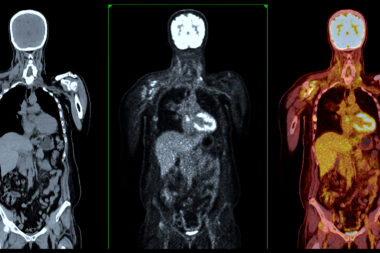

Explore the future of healthcare with microrobots for medical use, offering targeted drug delivery and improved navigation.